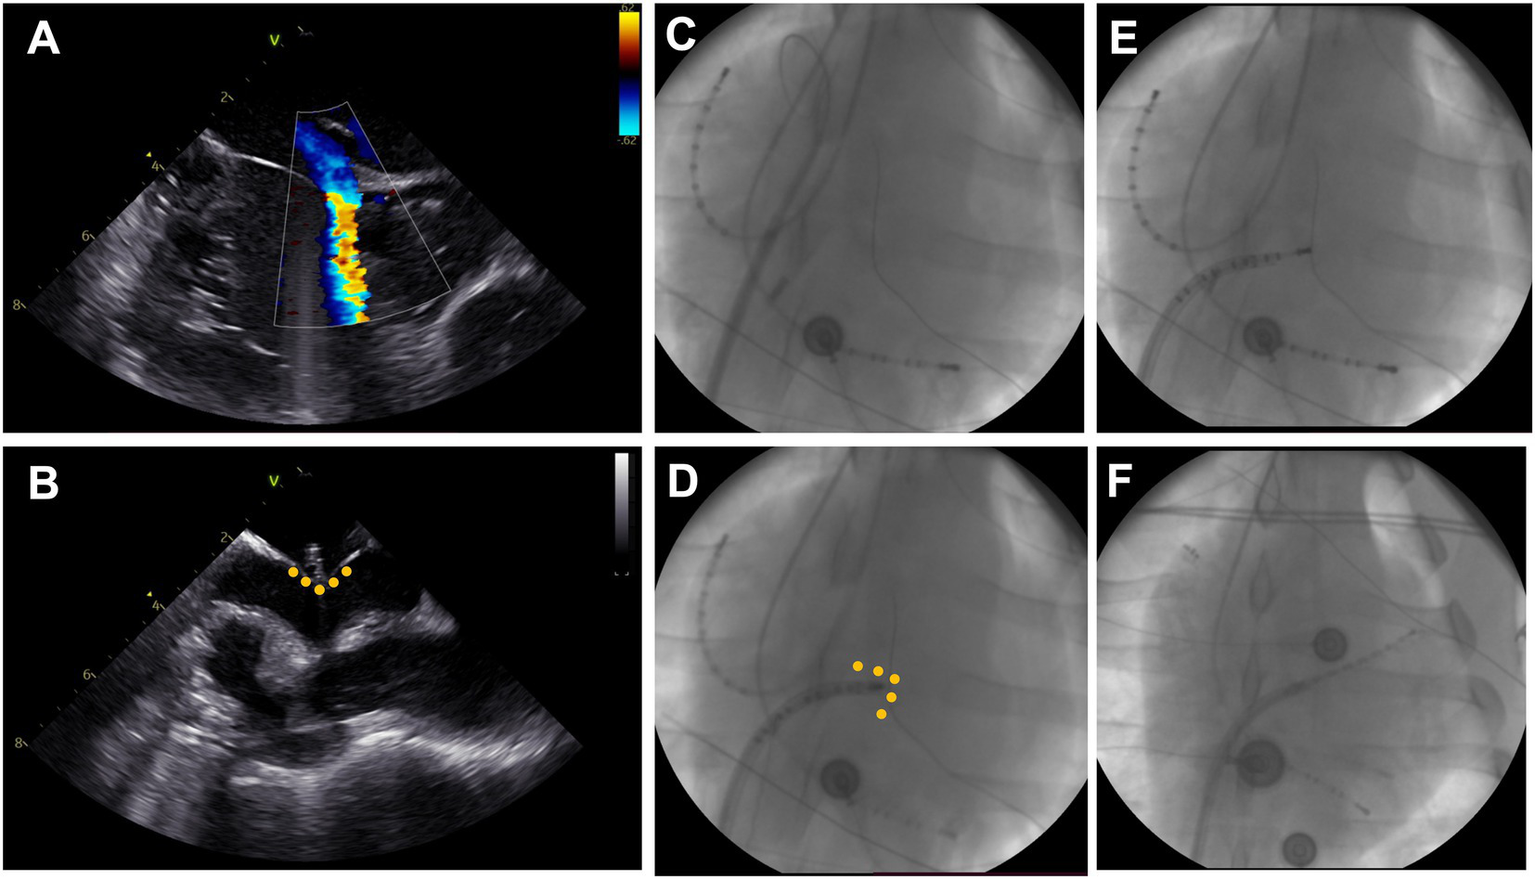

Transseptal puncture

Under fluoroscopic guidance (strict anterior–posterior projection) an intracardiac echocardiography (ICE) probe (ACUSON AcuNav™, Siemens, Muenchen, Germany) was advanced into the right atrium via the sheath in the left femoral vein to help visualize the interatrial septum (Figure 2). The short 8F sheath in the right femoral vein was exchanged for a long steerable sheath (Agilis NxT, 71 cm, medium curve, Abbott, Chicago, United States) and the wire advanced into the superior vena cava. Wire and dilator were removed, and a decapolar diagnostic catheter (Inquiry™, 6F, Abbott, Chicago, United States) introduced until the tip of the steerable sheath, which was deflected to 45°, turned to a 4 o’clock position and retracted into fossa ovalis. The diagnostic catheter was following advanced through the patent foramen ovale or pushed through the membranous part of the fossa ovalis, if possible. The transseptal passage was visualized in a subset of animals using ICE (Figures 2A–D). Successful transseptal puncture was verified with fluoroscopy (Figures 2E,F). The steerable sheath was advanced over the diagnostic catheter into the left atrium and flushed. In a subset of animals, selective pulmonary vein angiography, using a diagnostic coronary angiography catheter (Launcher 6\u00B0F, JL 3.5, 0.71″, Medtronic, Minneapolis, United States) and Visipaque 270 mg (GE Healthcare, Chicago, United States), was performed for illustration purposes. Finally, a multipolar mapping catheter (Advisor™ HD grid, Abbott, Chicago, United States) was introduced to perform the electroanatomic mapping.

Figure 2

Transseptal puncture. (A) Visualization of a patent foramen ovale with right-to-left shunt on intracardiac echocardiography (ICE). (B) ICE-Visualization of blunt transseptal puncture through fossa ovalis showing tenting (yellow dots) and narrow left atrium. (C) Fluoroscopy image in anterior–posterior projection with decapolar catheter in high right atrium (left top) and coronary sinus (bottom right). The steerable sheath is advanced into the superior vena cava over the wire. (D) The sheath is retracted to the fossa ovalis and a diagnostic catheter is advanced. (E) Blunt passage of the fossa ovalis using the diagnostic catheter. (F) Positioning of the diagnostic catheter in the left atrial appendage and advancement of the steerable sheath into the left atrium.

Successful and uneventful transseptal puncture and left atrial mapping could be performed in all 11 animals. In two animals, additional pulmonary vein angiography and in one animal, additional re-mapping after ablation was performed.

Due to the sagittal axis of the porcine heart in the thoracic cavity the ICE projections were rotated compared to normal projections in the human heart. Home view was found in a strict anterior angulation with the animal in a supine position. The interatrial septum was visualized with approximately 75–90° clockwise rotation of the probe. In 8/11 (73%) pigs, a patent foramen ovale was found and verified by leaflet separation and/or shunt in color Doppler mode (Figure 2).

In animals with a patent foramen ovale, transseptal access was achieved by advancing the ablation catheter through the patent foramen ovale. In the remaining animals, the left atrium was accessed by a blunt puncture through the membranous part of the fossa ovalis. For illustrative purposes, selective pulmonary vein angiography was performed in a subset of animals displaying a small left superior pulmonary branch, a large inferior common pulmonary trunk, and a common trunk for the right inferior and right middle branches (Figure 4).